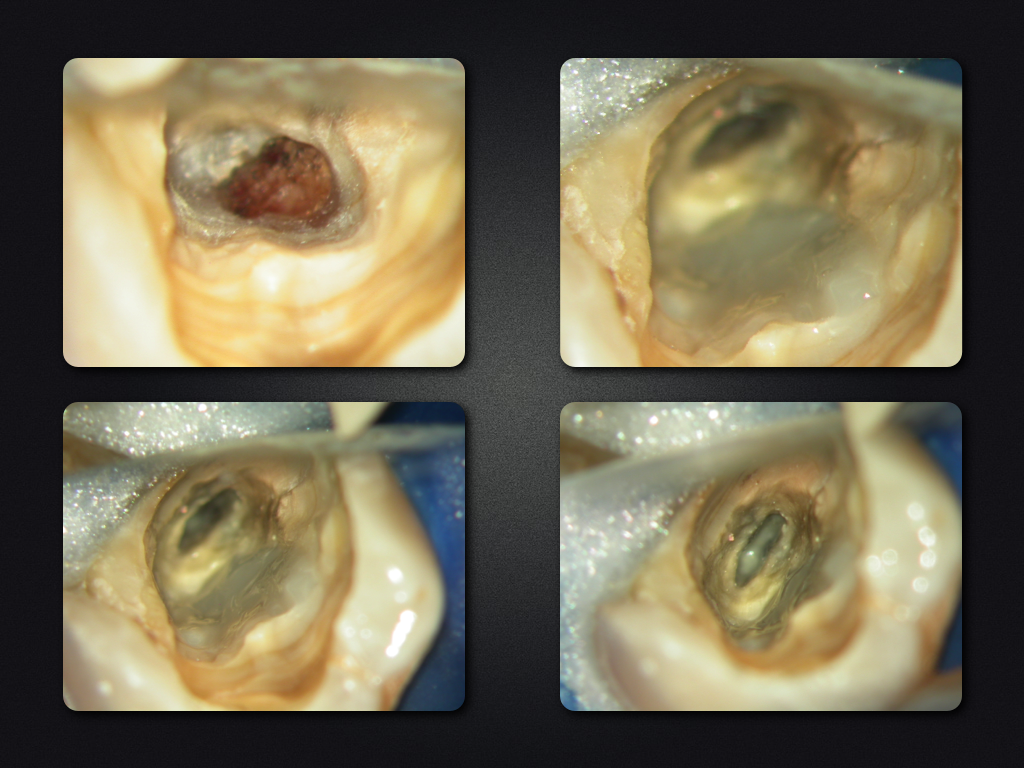

35D.006

2D zuzüglich 3D (V)